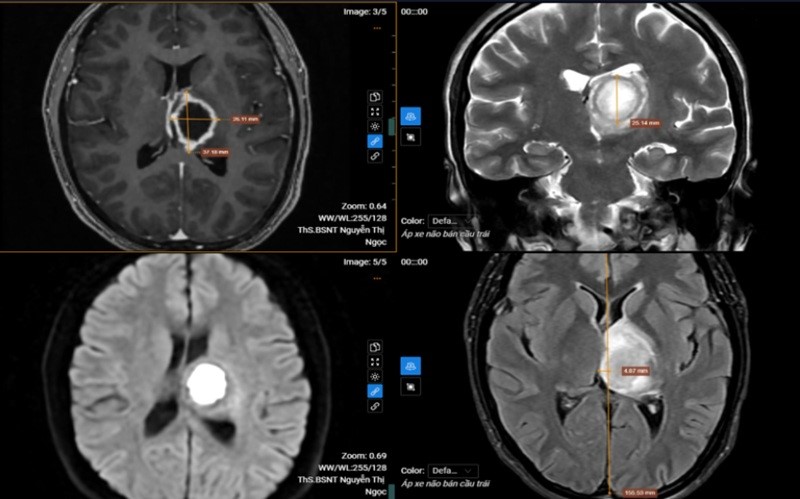

Kết quả MRI phát hiện tổn thương khu trú tại vùng đồi thị – vành tia bên trái.

Kết quả chụp cộng hưởng từ (MRI) sọ não phát hiện tổn thương khu trú tại vùng đồi thị – vành tia bên trái, kích thước khoảng 26x37x25 mm. Tổn thương dạng dịch, ranh giới rõ nhưng bờ không đều, trung tâm có hiện tượng hạn chế khuếch tán và ngấm thuốc viền sau tiêm. Vùng não xung quanh xuất hiện phù nề, tạo hiệu ứng khối làm đẩy lệch đường giữa của não sang phải khoảng 5 mm.

Sau khi hội chẩn chuyên môn, các bác sĩ chẩn đoán bệnh nhân mắc áp xe não bán cầu trái và chỉ định nhập viện điều trị nội trú theo phác đồ chuyên khoa để tránh nguy cơ tiến triển nặng. Khi nhận kết quả bệnh nhân đã rất “sốc” vì không nghĩ mắc bệnh lý nghiêm trọng tới vậy.